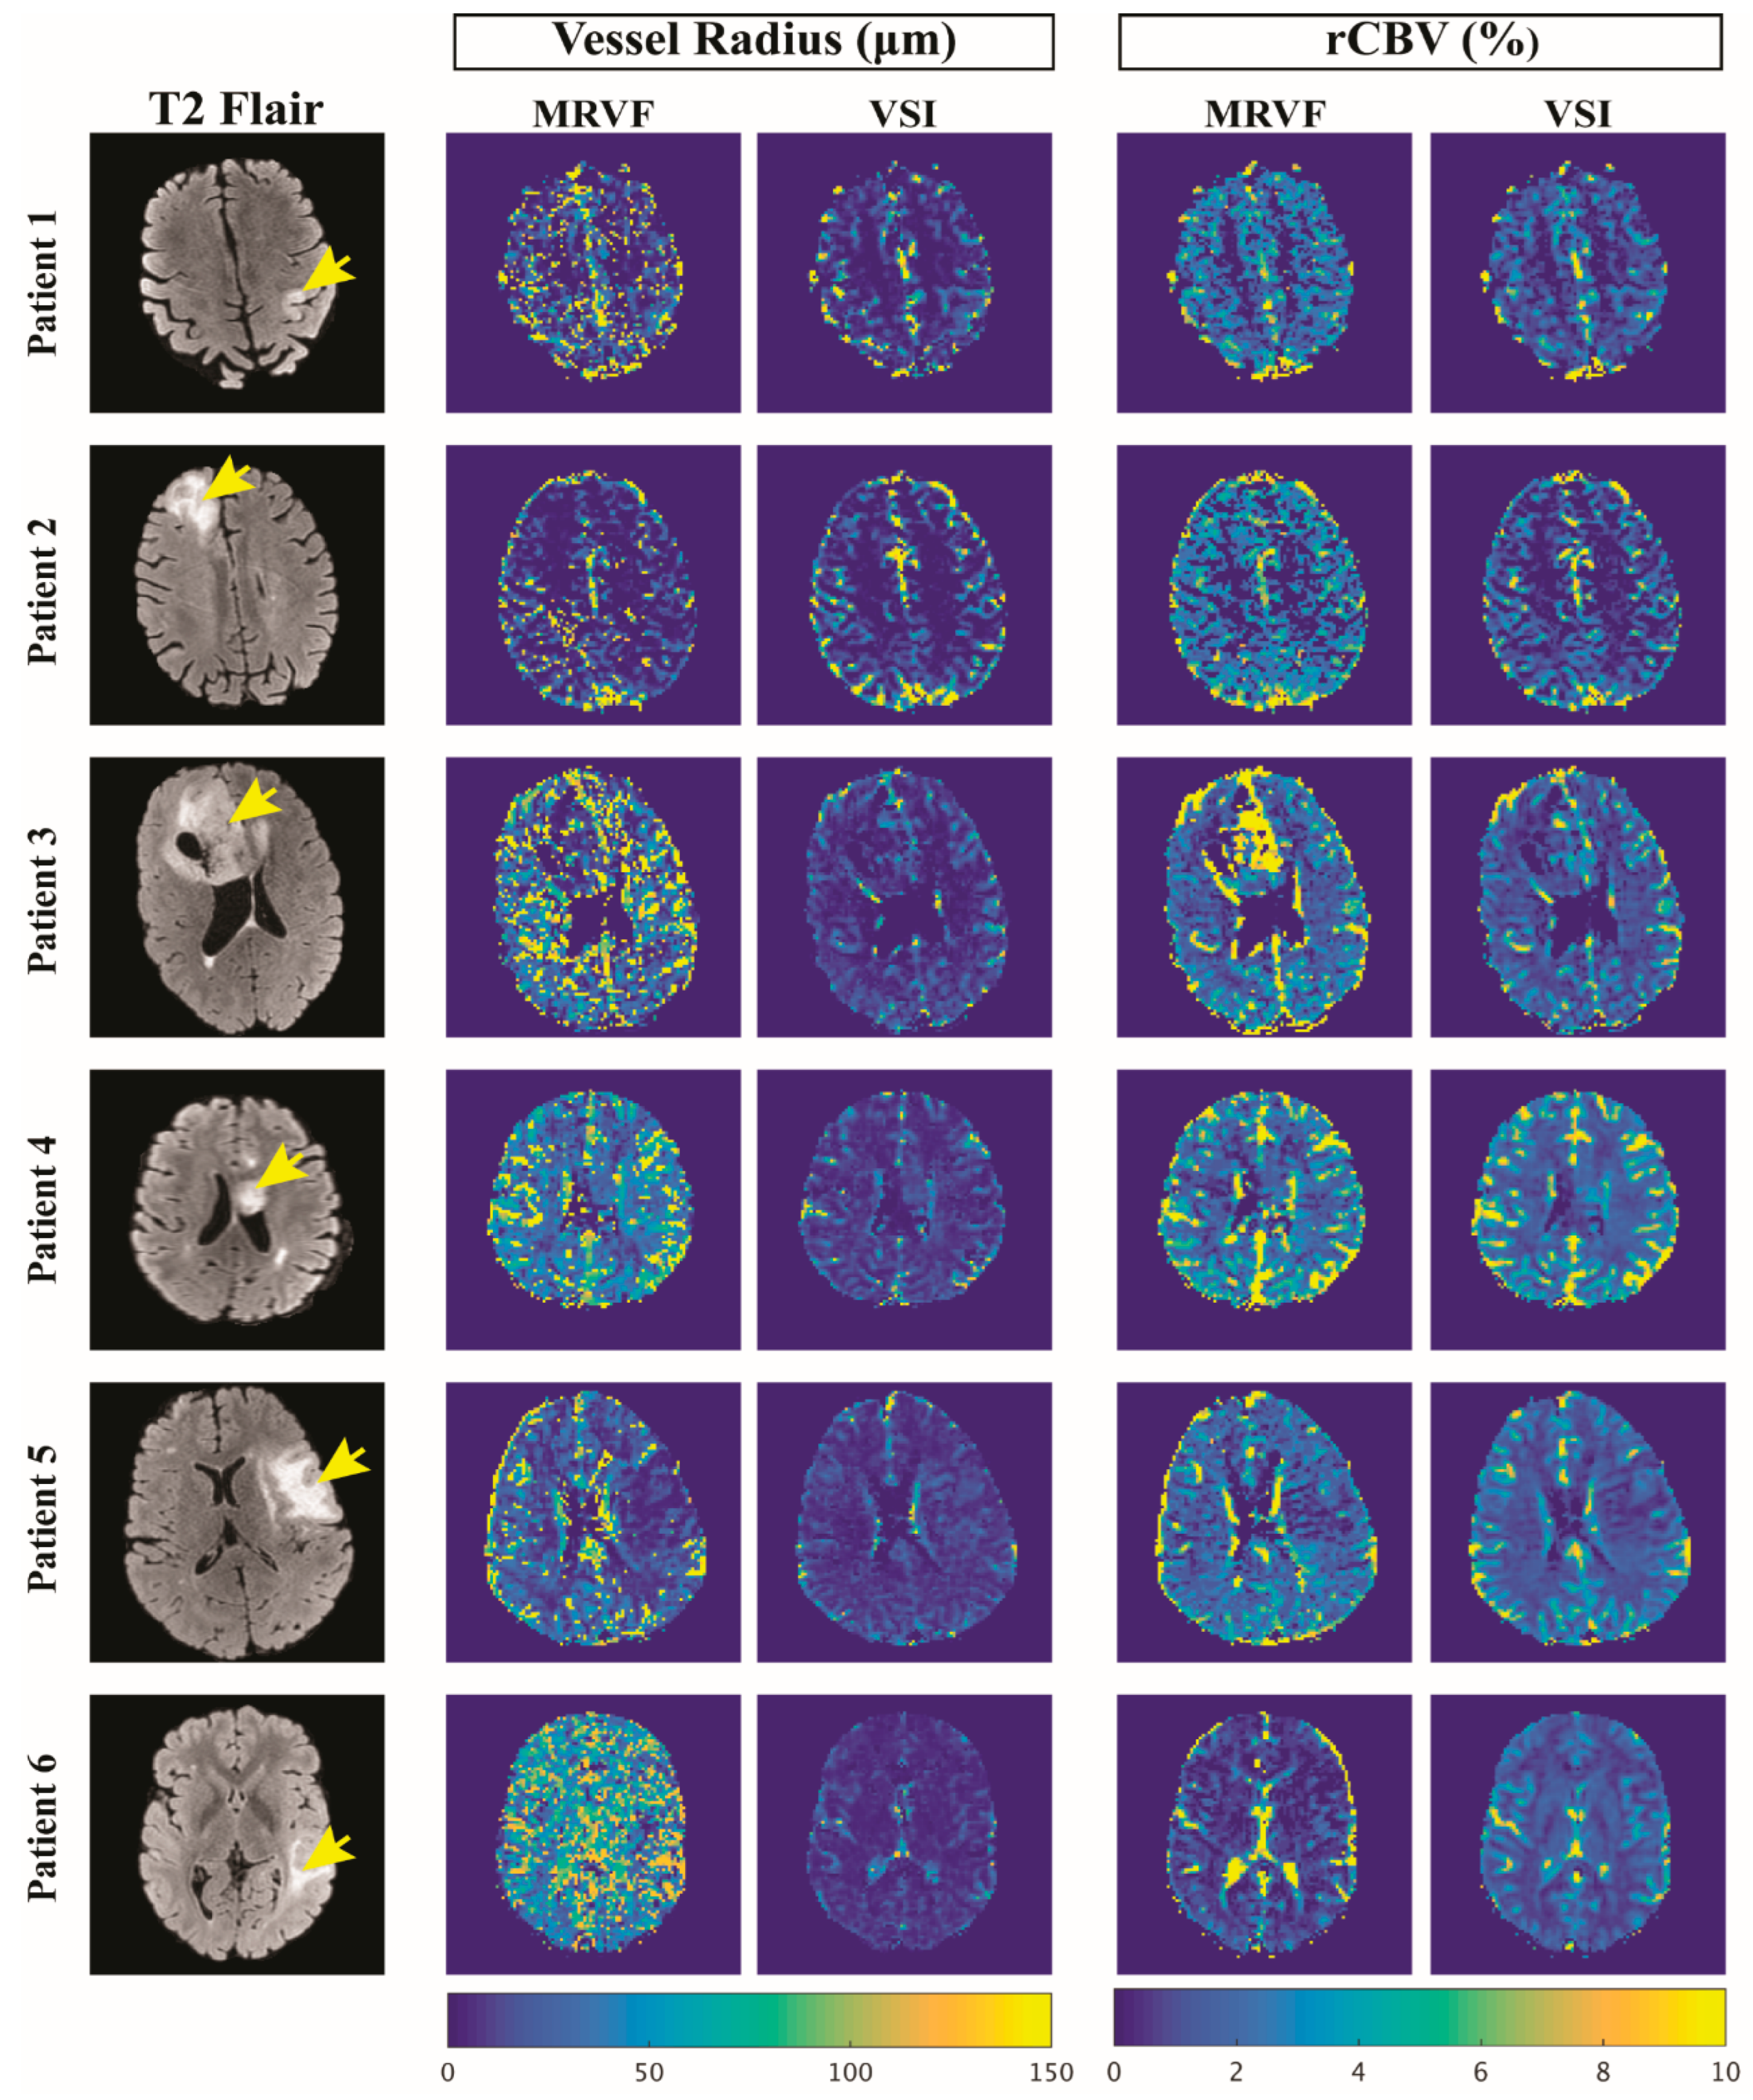

The GRE and SE time series and their dictionary match for tumor voxels in three example subjects are shown in Figure 3, and the graphs show the best match obtained from the dictionary for the tumor voxels. The rCBV and vessel radius parameter maps obtained with MRVF and VSI for all subjects are shown in Figure 4. The rCBV maps obtained via the MRVF technique clearly distinguish between the gray matter and white matter. Both techniques showed comparable patterns, although there were a few qualitative differences especially in patient 3, whose tumor had a high rCBV in the MRVF technique but not in VSI. The SSIM between MRVF and VSI in the R and rCBV for all subjects is presented in Table 2, and it can be observed that both techniques led to similar results as evidenced by the moderate-to-high SSIM values. The results of the Bland–Altman agreement analysis between the two techniques for mean parameter values in the whole brain and tumor regions for the six patients are shown in Figure 5. The analysis revealed a mean difference of 1.48% with the limits of agreement ranging from −0.03% to 3% for rCBV (p < 0.05 obtained with a paired t test performed between the mean rCBV between MRVF and VSI). For R, a mean difference of 10.9 µm with the limits of agreement ranging from −36.24 µm to 58.05 µm (p = 0.91 obtained with paired t test between the average R between the two techniques) was observed. This analysis showed a significant difference in rCBV between the techniques, while the difference was not significant for R with the MRVF and VSI.

Figure 4.

T2 FLAIR images of 6 patient datasets of slices showing the glioma (marked by the yellow arrows) and the corresponding vessel radius (in μm) and rCBV (in %) maps obtained using the MRVF and the VSI methods.

Although both techniques (MRVF and VSI) yielded similar rCBV maps for the gray and white matter in all patients (Table 2), a significant quantitative difference was obtained in one patient (Figure 4) with an enhancing glioma. Although our VSI implementation did include a leakage correction, this was previously proven to be sub-optimal in high-grade tumors with high vascular permeability [29,30,31]. The dictionary in MRVF did, however, include permeability as an input parameter for the simulations, and this might explain the observed differences in rCBV in the tumor region. For this reason, we favor MRVF, as CA leakage is explicitly included in the simulation. The use of a preload dose minimizes leakage effects, although it has been shown previously that preloading could lead to an underestimation of rCBV [32]. The fact that patient 3 had a different glioma type and molecular profile compared to the other two patients with enhancing tumors (Table 1) could also be a possible factor for this significant difference in parameter maps between the two techniques. Since the current study was limited to only three patients with an enhancing tumor, the factors that cause differences in rCBV values warrant further investigation by applying the technique to more datasets and preferably with a comparison to a gold-standard measurement, which is unfortunately difficult to obtain.